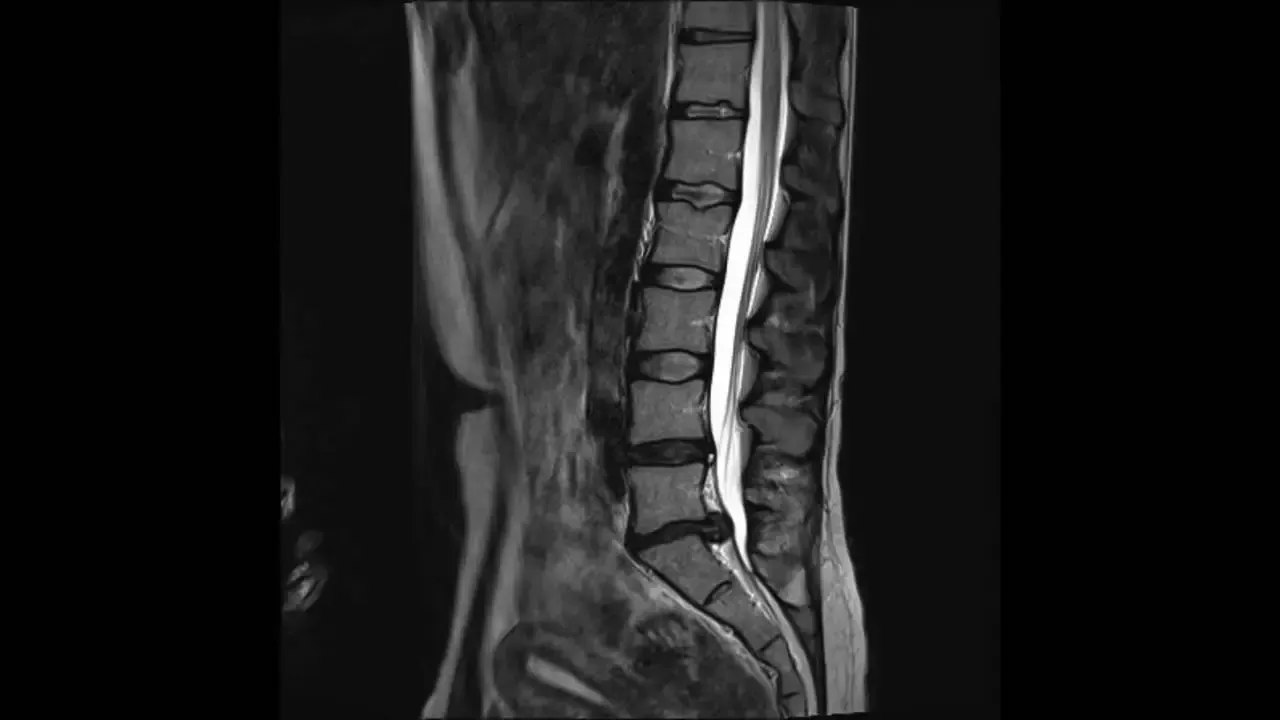

Disklerde dejeneratif sinyal kaybı, disklerde yaşanan mekanik veya yapısal bozulmalar sonucu meydana gelen bir problemdir. Bu durum, disklerin sinyal iletimini etkileyerek çeşitli sağlık sorunlarına yol açabilir. Disklerde dejeneratif sinyal kaybının en yaygın belirtileri arasında ağrı, hareket kısıtlılığı ve sinir sıkışması yer alır. Risk faktörleri arasında yaşlanma, genetik yatkınlık, aşırı kilo ve yanlış postür gibi unsurlar bulunmaktadır. Bu faktörler, disklerin zamanla dejenerasyona uğramasına ve fonksiyon kaybına neden olabilir. Belirtilerin erken tanınması ve uygun tedavi yöntemlerinin uygulanması, disklerde dejeneratif sinyal kaybının etkilerini azaltmada kritik öneme sahiptir.

Disklerde Dejeneratif sinyal kaybı, omurgadaki disklerin yapısında meydana gelen bozulmalar sonucu oluşan ve sinyal iletiminde kayba yol açan bir durumdur. Bu bozulmalar genellikle yaşlanma, aşırı kullanım veya yaralanmalar gibi nedenlerle ortaya çıkar. Disklerin düzgün işlev görmemesi, vücut tarafından gönderilen sinyallerin etkili bir şekilde iletilmesine engel olur. Sonuç olarak, bireylerin günlük yaşam kalitesinde belirgin bir düşüş yaşanabilir.Bu tür sinyal kaybının temel belirtileri fiziksel rahatsızlıklarla kendini gösterir. Çoğu zaman, hastalar bel ağrısı, bacaklarda uyuşma veya güçsüzlük gibi şikayetlerde bulunurlar. Bu durum, kişinin hareket kabiliyetini ve genel sağlığını olumsuz yönde etkileyebilir. Erken teşhis ve müdahale, belirtilerin hafifletilmesi adına son derece önemlidir.- Disklerde Dejeneratif Sinyal Kaybının Belirtileri